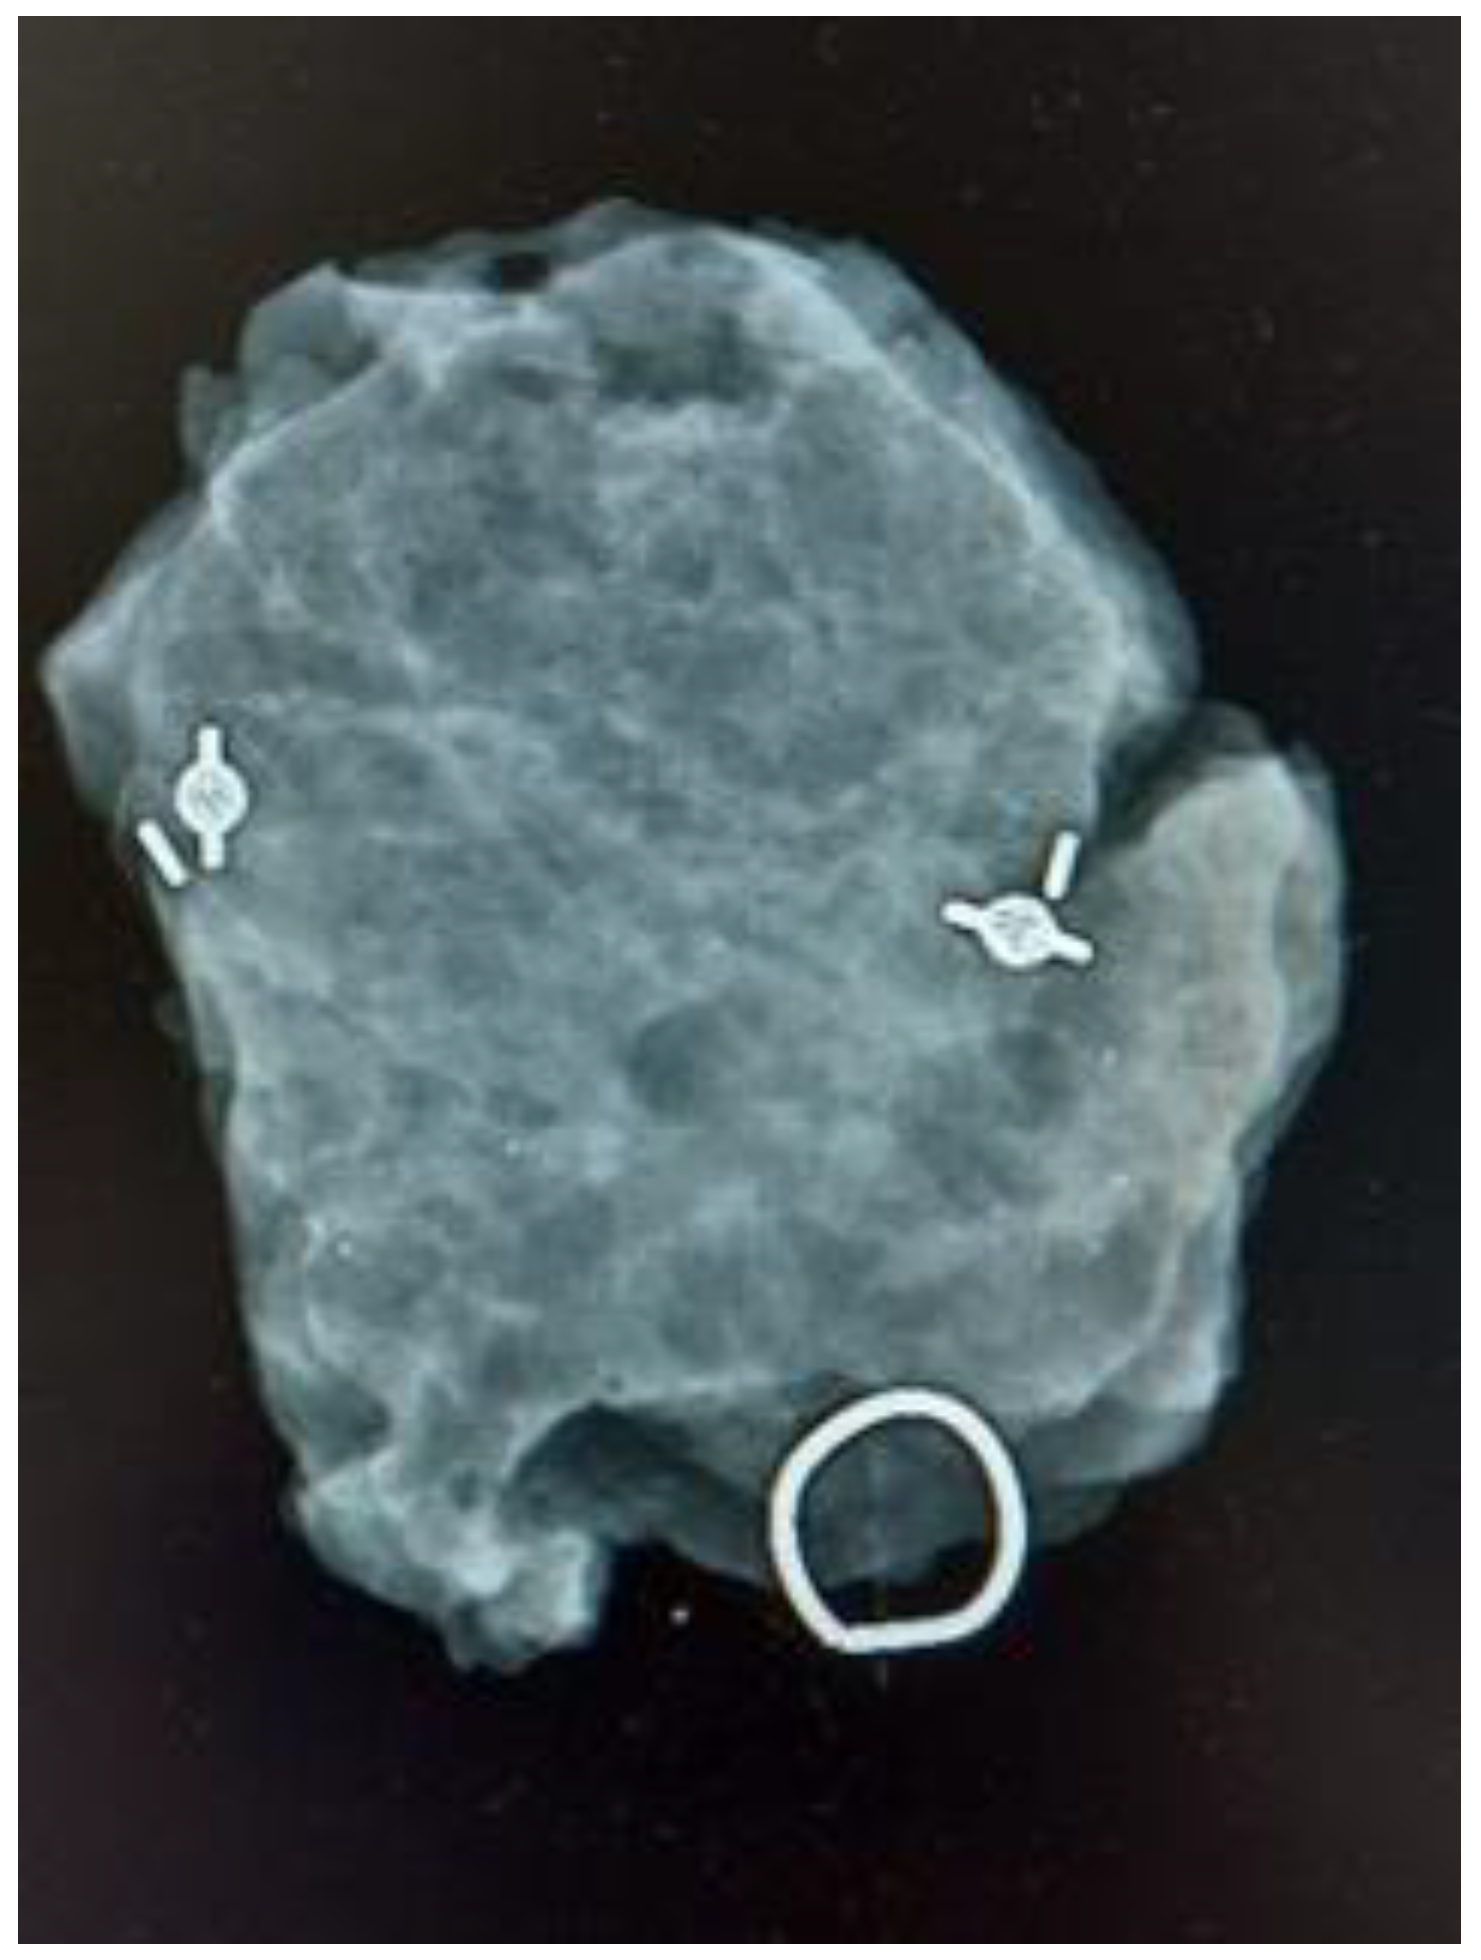

A total of 225 patients that underwent BCS for non-palpable breast lesions were included in the study; 149 surgeries were MS-guided, and 76 were wire-guided. No incidence during the placement of MSs or wires was reported, being accurately placed in all cases either centrally or laterally to the lesion. The tumor was localized and excised in every case. In six cases, two MSs were placed to guide excision: in four cases, two coils were placed prior to neoadjuvant treatment for marking purposes, and in two patients, they were placed to delimit an area of microcalcifications with confirmed diagnosis of intraductal carcinoma (Figure 3). Both cohorts exhibited similarity in terms of clinical and pathological characteristics. In the MS group, the median age was 65 years (range 28 to 85), while in the wire group, it was 60 years (range 39–90), with no statistical difference found (p = 0.60).

Figure 3.

Control mammogram of a surgical specimen guided with two magnetic seeds.

We successfully reported the placement of the MS in the lesion, either centrally or laterally, as well as the detection of the MSs and excision of the lesion in every case. No complications were registered during MS placement or excision. Additionally, we utilized MSs for bracketing breast lesions, understood as bracketing the placement of two or more MSs to delimitate the boundaries of a tumor lesion that we want to excise [16]. The bracketing technique was first described with wires, but has been reported with other devices such as MSs and radioactive seeds [17,18]. We report six cases in which two MSs were placed to guide excision: four cases in which two coils were placed prior to neoadjuvant treatment for marking purposes, and in two patients, they were placed to delimit an area of microcalcifications with a confirmed diagnosis of intraductal carcinoma. In every case, both magnetic seeds were excised in the surgical specimen.